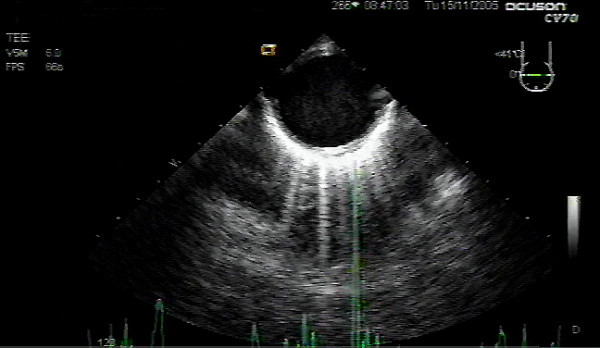

How do you obtain the ME Ascending Aorta in Short Axis?

Insert the probe to the ME, sector depth 10-12cm, angle 0°

From ME AV SAX (30°), withdraw probe (ascending aorta SAX), rotate the omniplane angle back to 0° (Anteflex a little bit)

Why is the Left Pulmonary Artery not visualized well in the ME Ascending Aorta Short Axis?

Bronchial and Tracheal tree is obstructing the view